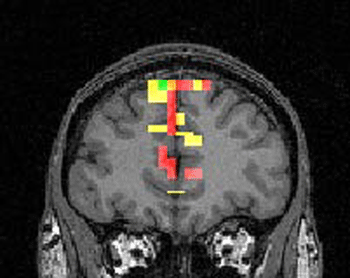

![]()

Le cortex frontal et les aires sensorielles restent en activité pendant

l'intégration et le traitement des informations sensorielles lors

du fonctionnement de la mémoire de travail.

Nous savons que de nombreuses aires corticales sont impliquées dans la mémoire de travail en fonction de la modalité sensorielle du stimulus (visuel : pariétal, auditif : temporal…)